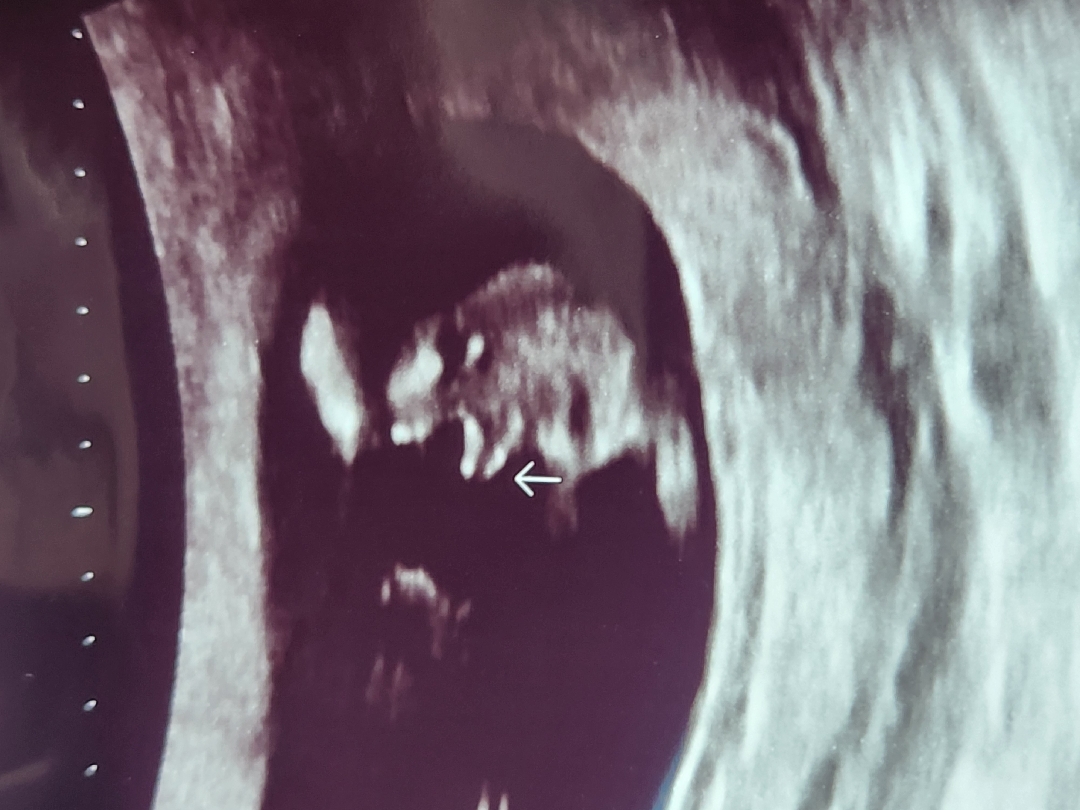

๐ถ์ผ๊น์..?

13์ฃผ์ฐจ์ ๋๋ค! ์ค๋ ์ด์ํ ๋ณด๊ณ ์๋๋ฐ...๐ ์์ง ํ์ค์น ์๋ค๊ณ ๋ ํ์ จ๋๋ฐ ๊ณ ์ถ..๋ง๋๊ฒ๋๊ฐ๊ณ ...ใ ใ ใ ใ ๐คฃ ์ ๋ฐฐ๋๋ค ์ด๋ ์ ๊ฐ์